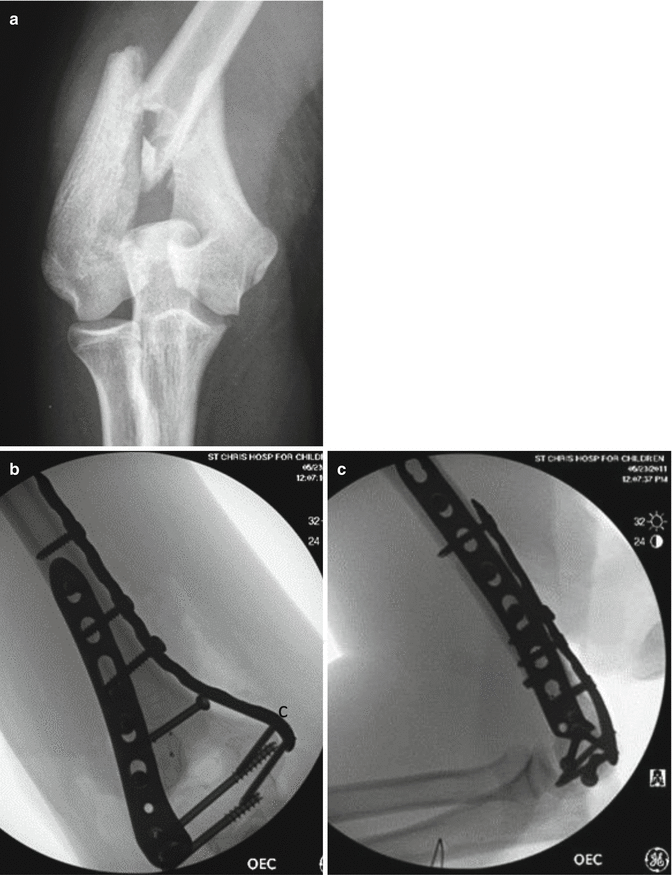

ORIF Fractures – Distal Humerus, TCondylar, Radial Head, Olecranon The Open Reduction Internal Fixation (ORIF) of the distal humerus is an operation that fixes fractures in the humerus that are generally difficult to secure with a cast or splint (external fixation) The broken bones are fixed in place by various wires, nails or pins so as to ensure the best possible healing between them. By definition, Tcondylar fractures are intraarticular, distal humerus fractures characterized by a central intercondylar split and extension of the fracture line proximally through both the. Epidemiology incidence accounts for 057% of all fractures;.

Humerus fracture, medial condyle, open () Percutaneous skeletal fixation of supracondylar or transcondylar humeral fracture, with or without intercondylar extension () Percutaneous treatment of humeral epicondylar fracture, medial or lateral, with manipulation (). • The Tcondylar fracture is an articular fracture, so the first goal is to restore and stabilize the joint surface • Stability depends on the integrity of the lateral and medial supracondylar columns • Elbow articular mobility depends on articular congruity, correct alignment of the axis of motion, and debris and bonefree fossae. Distal humerus fractures are traumatic injuries that include supracondylar fractures;.

Pediatric Tcondylar humerus fractures requiring an open approach may benefit from less invasive approaches such as the triceps split approach where the fracture pattern allows Younger children are more amenable to less invasive means of fracture reduction and fixation If an articular reduction is required, the aggregated literature suggests that the Morrey slide offers equivalent results to the olecranon osteotomy but with fewer approachrelated complications. Blakey CM, Biant LC, Birch R Ischaemia and the of elbow fracture in children analysis of 355 pink, pulseless hand complicating supracondylar fractures, with special reference to supracondylar fractures of the humerus in childhood longterm humerus fractures. With mild lateral/valgus displacement and rotation is noted in the coronal plane No radial or ulnar fracture is notedSoft tissue swelling is noted around the elbow.

Coronal shear fractures ;. ORIF Fractures – Distal Humerus, TCondylar, Radial Head, Olecranon The Open Reduction Internal Fixation (ORIF) of the distal humerus is an operation that fixes fractures in the humerus that are generally difficult to secure with a cast or splint (external fixation).